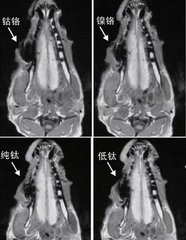

烤瓷牙的內(nei) 冠和外冠材料不同,外冠是瓷的,內(nei) 冠有金屬、合金以及瓷的。比如說鎳鉻合金、鈷鉻合金、鈀金合金、金合金等材料可能會(hui) 對核磁共振成像有不同程度的幹擾。尤其是前麵兩(liang) 種比較嚴(yan) 重,後兩(liang) 者稍微好一些,而瓷材料不含金屬,所以沒有影響。

種植牙的材料分為(wei) 牙根、基台和牙冠三部分,牙根和基台的材料通常是純鈦或者是鈦合金,這類材料對核磁共振成像影響小,而上部的牙冠有金屬和全瓷材料,建議盡量選擇全瓷材料,就不會(hui) 對核磁共振有影響了。